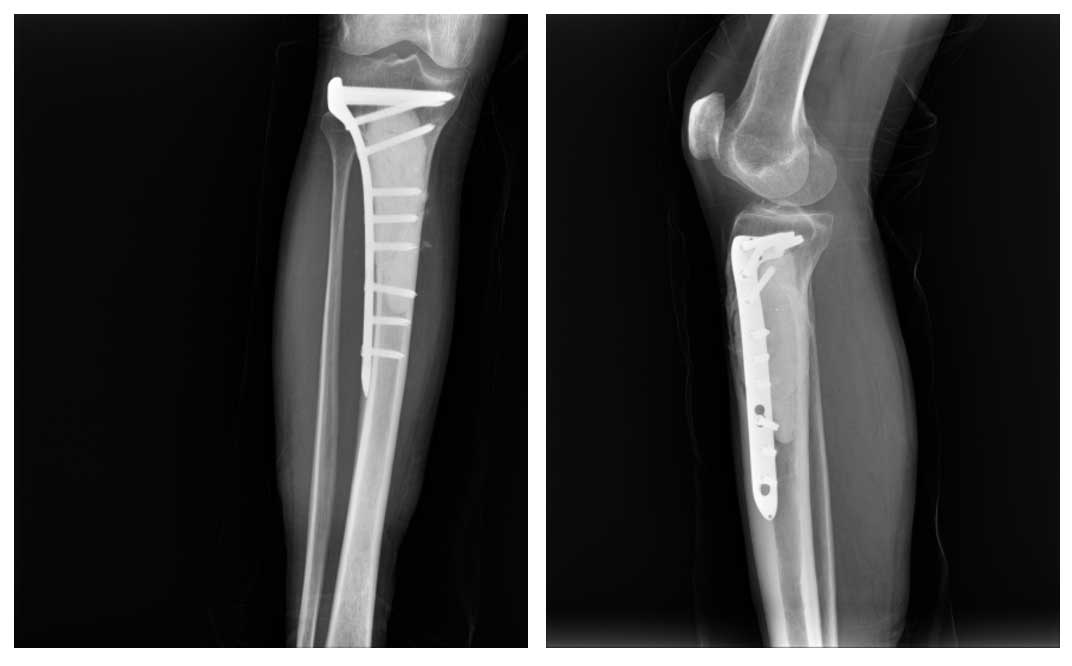

Tümörlü bölge agresif küretaj ile temizlendi, oluşan boşluk kemik çimentosu ile dolduruldu ve anatomik plak ile güçlendirildi. Ameliyat başarıyla tamamlandı.

Ameliyat sonrası hasta birinci günde güvenle yürütüldü ve sorunsuz taburcu edildi. İkinci haftada dikişleri alınarak, tamamlayıcı tedavi amacıyla radyoterapiye yönlendirildi.

Ameliyat Sonrası: Tümörün temizlenip oluşan boşluğun kemik çimentosu ile doldurulması ve anatomik titanyum plak ile güçlendirilmesi görülmekte.